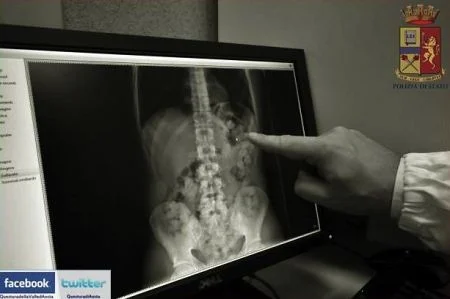

AOSTA. Stava trasportando della droga sul treno Torino-Aosta quando, poco dopo Saint-Vincent, è stato fermato per un controllo e ha deciso di ingoiare una quindicina di ovuli. Abdou Ndiaye, un cittadino senegalse di 29 anni (non 26 come indicato in precedenza), è stato arrestato lo scorso martedì pomeriggio dalla Squadra mobile per detenzione di stupefacenti ai fini di spaccio. E' ora piantonato in ospedale.